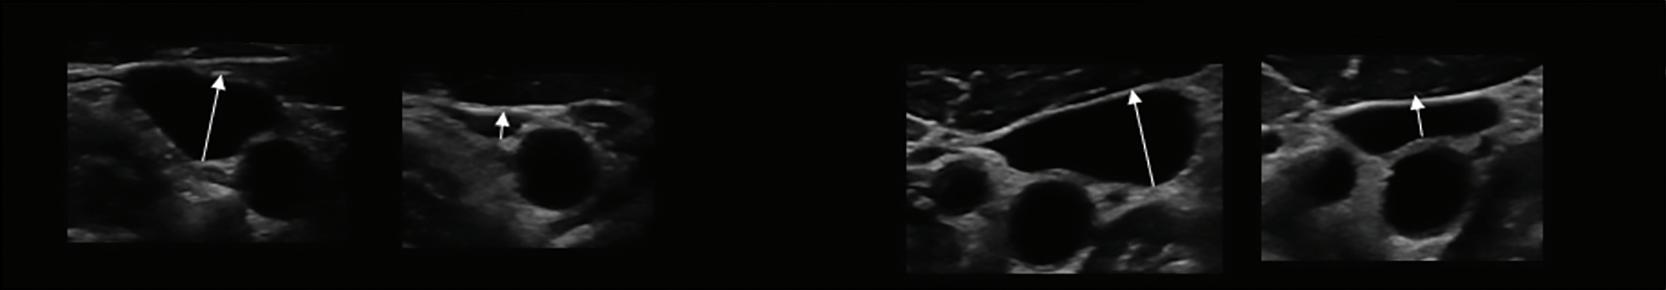

Imaging in Heart Failure with Preserved Ejection Fraction: A Multimodality Imaging Point of View

Serkan Ünlü, Özge Özden and Ahmet Çelik

Role of Imaging in Cardiomyopathies

Vincenzo Castiglione, Alberto Aimo, Giancarlo Todiere, Andrea Barison, Iacopo Fabiani, Giorgia Panichella, Dario Genovesi, Lucrezia Bonino Alberto Clemente, Filippo Cademartiri, Alberto Giannoni, Claudio Passino, Michele Emdin and Giuseppe Vergaro

DOI: https://doi.org/10.15420/cfr.2022.26